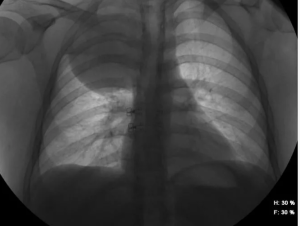

Установлено, что у больной Б-н, 47 лет, предыдущее рентгенологическое обследование органов грудной клетки проводилось 3 года тому назад и патологии со стороны легких не отмечалось. В торакальном отделении ей проведена рентгенография легких и установлено, что в 10 сегменте левого легкого определяется округлой формы тень, средней степени интенсивности, с нечеткими контурами, размером 3,6х3,3см. Корни и средостение не расширены.

Другие легочные поля обычные. Дважды была проведена бронхоскопия и установлено, что левый нижний долевой бронх сужен опухолевидным образованием, содержит слизь, слизистая оболочка сохранена. МСКТ грудной клетки: в нижней доле левого легкого определяется округлое образование 35х32 мм, не отграниченное от корня; 8 и 9 сегментарные бронхи сужены (рис.1). Заключение: КТ -картина рака нижней доли левого легкого. Цитологическое исследование бронхоальвеолярного смыва: слизь, группы клеток призматического эпителия; раковые клетки не выявлены; общее количество клеток в смыве 0,05х10х6/л: лимфоциты - 4%, нейтрофилы - 74%, альвеолярные макрофаги - 22%.